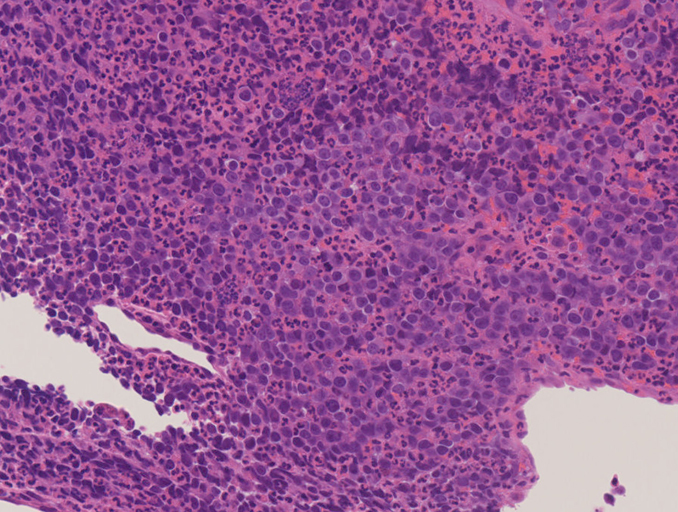

処置: 気管支内視鏡検査で,1.左肺腫瘍からTBB (VS1),2.腫瘍と一塊になったリンパ節からEBUS-TBNA (VS2),を施行された.

CT画像および肺腫瘤生検組織